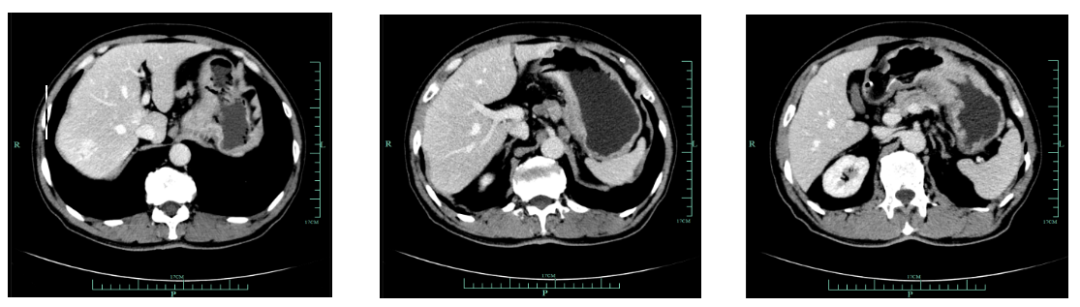

现病史:1月余前出现吞咽哽噎,无饮水呛咳,偶感腹胀腹痛,无恶心呕吐等不适,至外院就诊,上腹部增强CT(2018-12-14)提示:胃小弯及贲门壁异常,提示胃癌。胃周多发肿大淋巴结转移考虑。

既往史(续):全腹部CT平扫+增强提示胃贲门部及体部胃壁增厚,结合临床考虑胃癌伴胃周及腹膜后多发淋巴结转移;肝脏多发血管瘤。

入我院后全面进行评估(2019.4):全腹部CT平扫+增强评估提示腹膜后,胰腺周围多发淋巴结增大,淋巴结转移考虑。

2020-11-3全腹部CT平扫+增强提示胃癌术后改变,术周及腹膜后多发肿大淋巴结显示,对照2020-7-7CT淋巴结肿大进展,结合临床疗效评估PD。